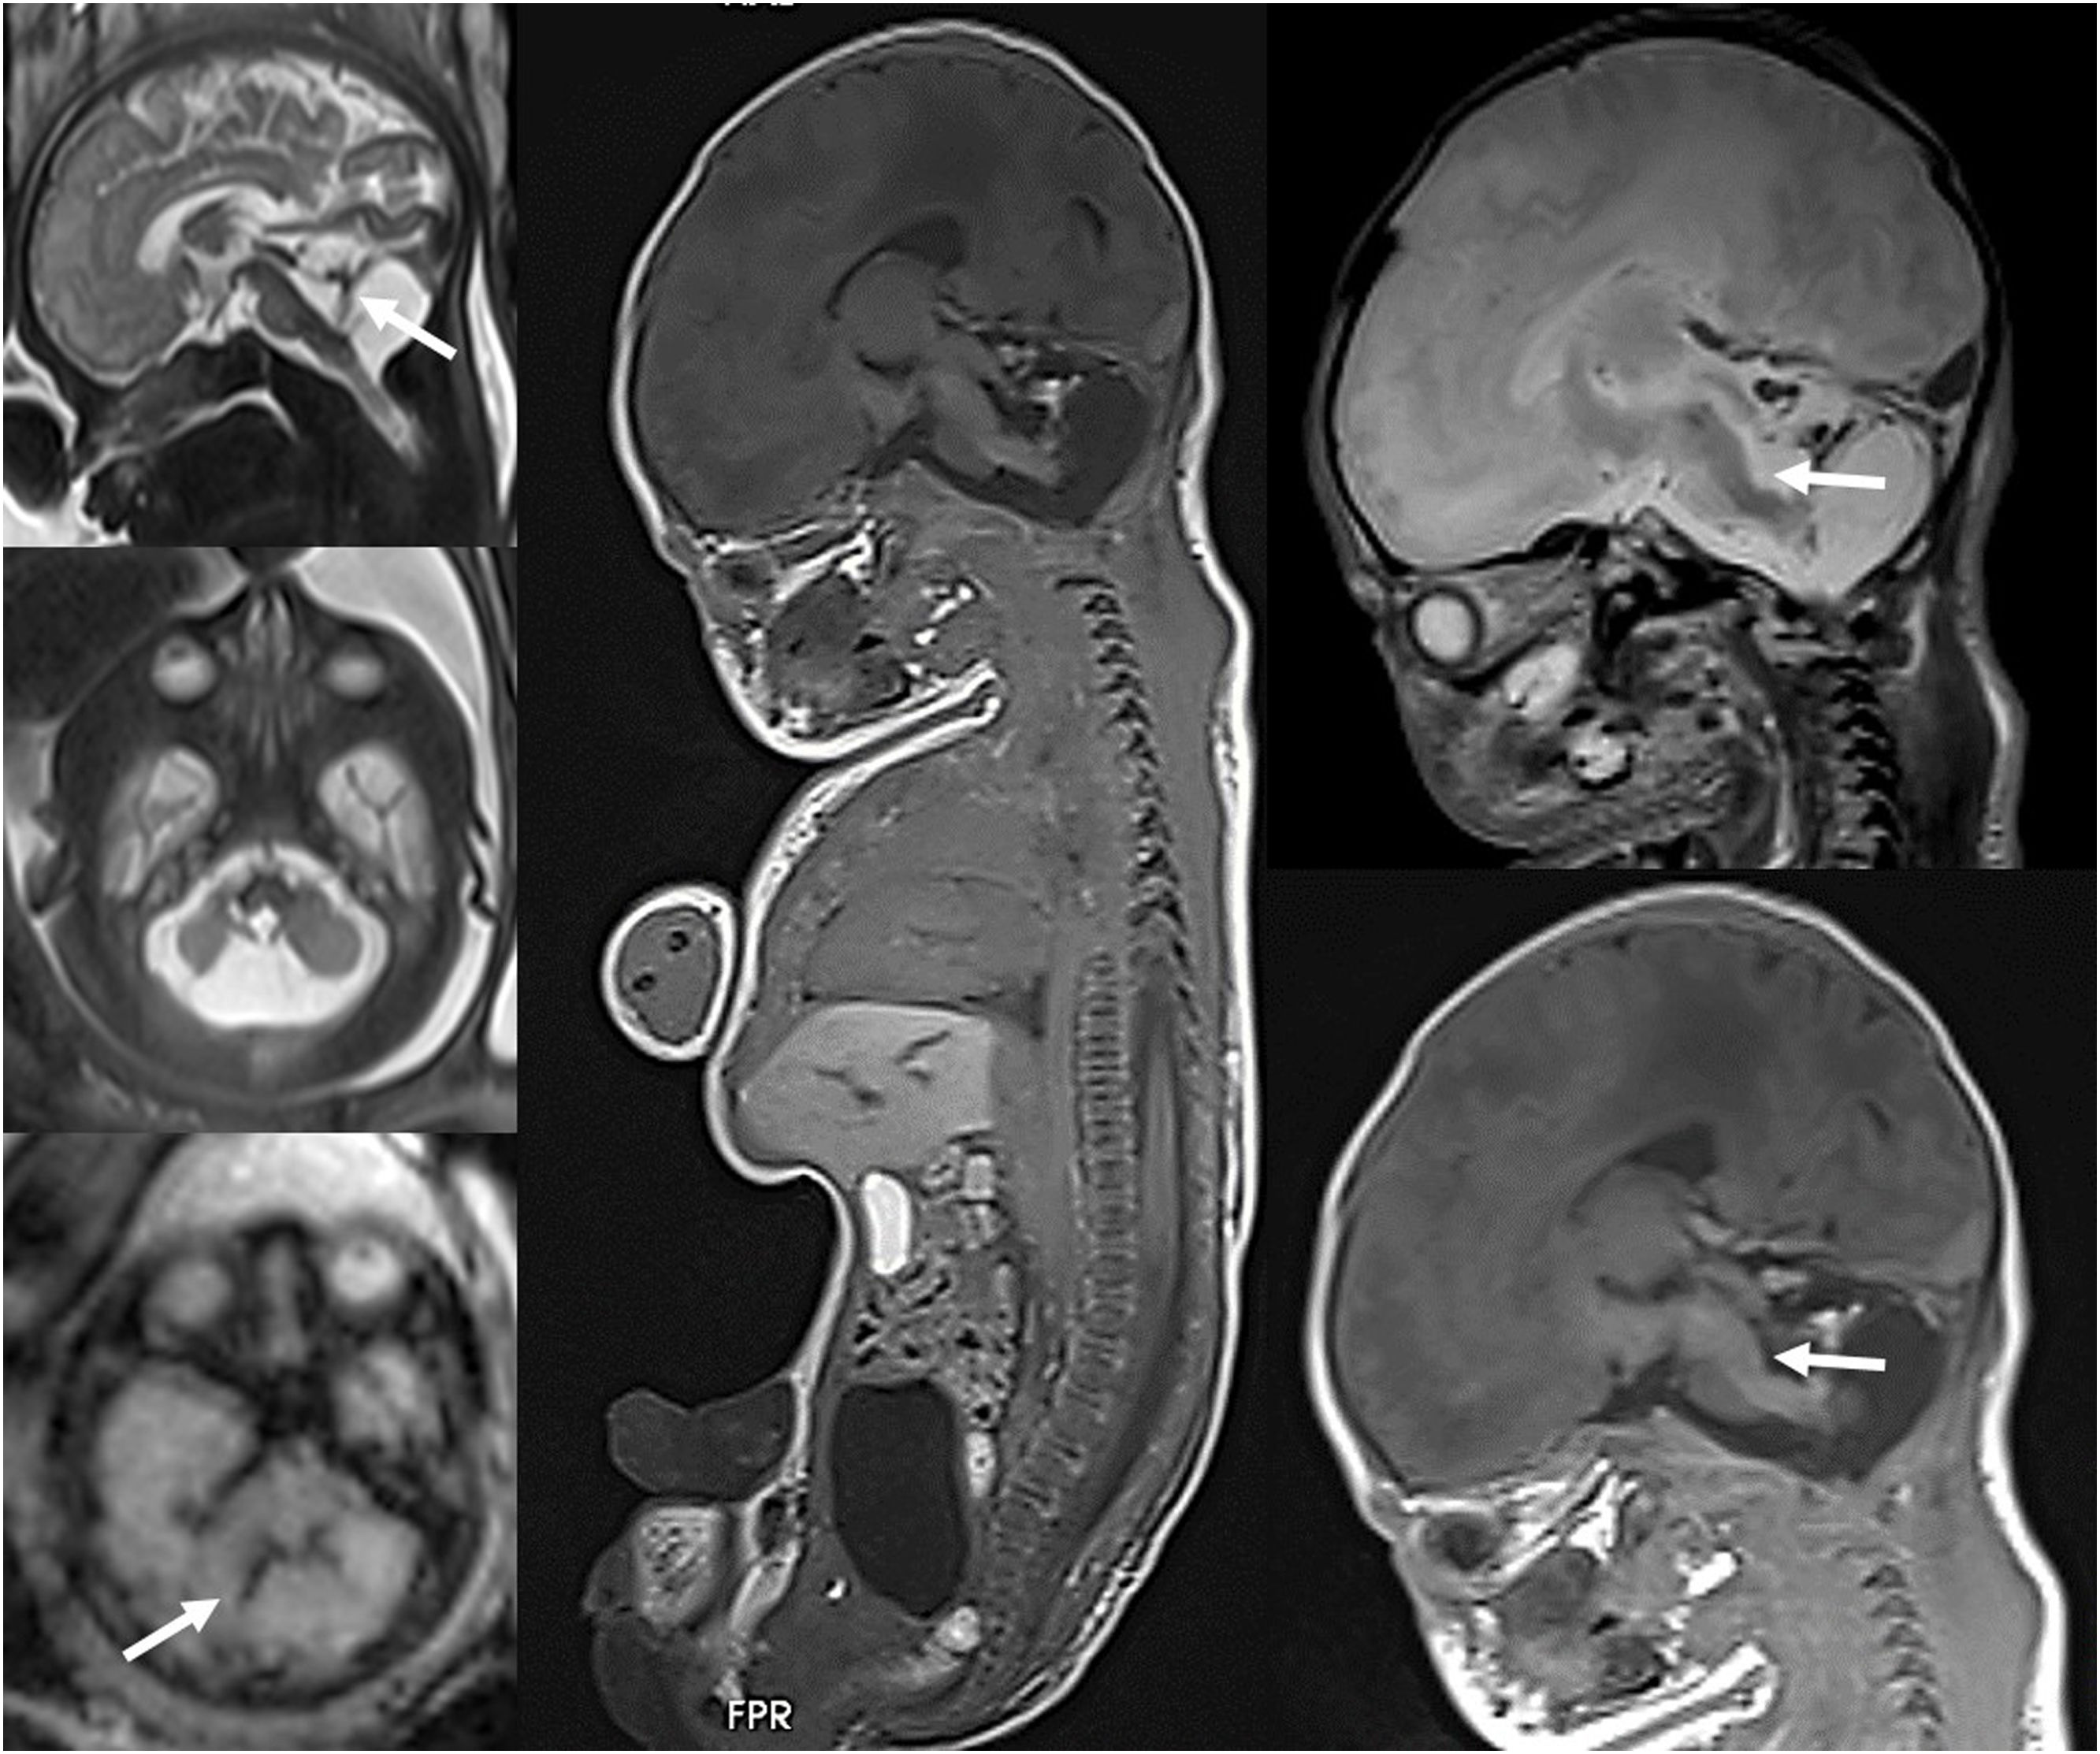

Fetal MRI is already widely used as the second-line imaging technique following the obstetric ultrasound, chiefly to characterize central nervous system anomalies, although it should be preferentially performed in tertiary care hospitals by experienced radiologists and its use before 19–20 weeks of gestation is not recommended. The integration of MRI data with genetic and statistical data is now necessary to provide adequate prenatal counseling.

Advances in post mortem imagingPediatric post mortem (PM) imaging is an emerging technique whose use has increased as performance of invasive autopsies has decreased and the acceptance of PM imaging has increased among parents and health professionals. It includes different modalities, such as plain radiography, CT or MRI. Plain radiography continues to be the mainstay of forensic PM imaging in suspicious childhood deaths. Numerous studies have demonstrated the utility of MRI for perinatal and fetal post mortem imaging due to its capacity to visualize soft tissue anomalies, although PM CT offers advantages for identification of fractures, with a lower cost and a shorter acquisition time.4 The United Kingdom guideline for cases of suspected child abuse was updated in 2018 and now recommends performance of a PM CT scan if skeletal trauma is suspected but was not detected by plain radiography, as well as performance of PM MRI if soft-tissue trauma is suspected in the context of unexpected childhood death. Post mortem MRI is performed in fetuses or newborn infants, preferentially with whole body imaging within 24 h of birth or death (Fig. 3). Previous training in PM imaging is required to recognize normal PM findings and differentiate them from truly pathological findings. Post mortem imaging may not be diagnostic in fetuses of young gestational age.

Fetus at 33 weeks of gestational age with sonographic findings indicative of cerebellar hypoplasia. (A) Fetal MRI performed at 33 weeks showing a destructive cerebellar lesion with blood remnants (arrows). (B) Post mortem fetal MRI conducted after the pregnancy was terminated showing the cerebellar hemorrhage associated with a tegmental lesion of the medulla oblongata (arrows) that was previously undetected.